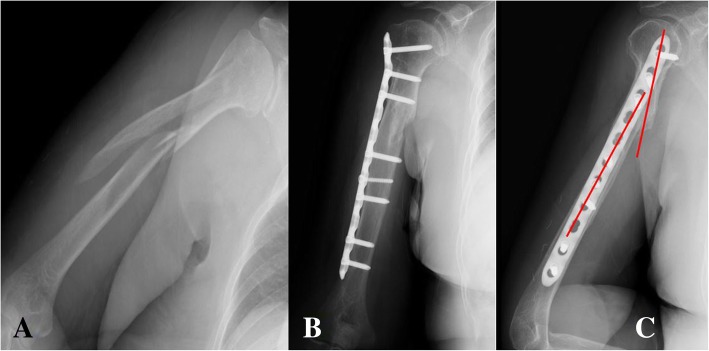

Fig. 1.

In MIPO technique using the narrow locking compression plate, intraoperative bending of this locking plate could adequately fitted to long spiral (Complex spiral type, AO classification: C1) humerus shaft fracture with proximal fracture extension to the greater tuberosity (a). However, at the postoperative lateral x-ray, the fracture angulation could be found after non-anatomical narrow locking compression plate fixation (b, c)